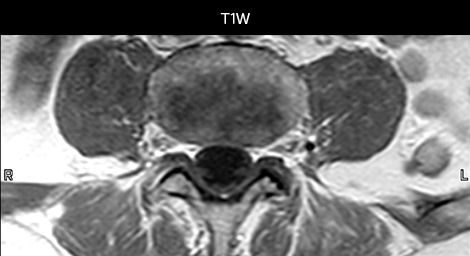

cervical spine mri in ed

Cervical spine routine exam

This patient presented with headache that was worse with neck flexion and we see a Chiari 1 malformation with low-lying cerebellar tonsils as well as some degenerative cervical thrombolytic change.